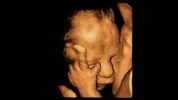

A murdered unborn human in an early stage of development.